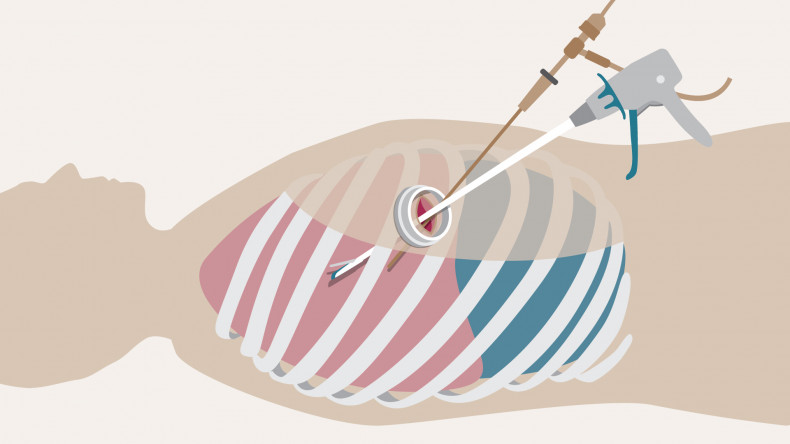

Single-port (also known as single-incision) video-assisted thoracoscopic surgery is a minimally invasive keyhole surgical procedure that can be used to remove lung cancers.

Video-assisted thoracoscopic surgery (VATS) offers lung cancer patients a minimally invasive option to remove parts of the lungs affected by cancer to help prevent the spread of the disease.

Single port (or single incision) VATS offered at our centre, is a keyhole surgery procedure, where a camera and surgical instruments are inserted into the chest via one small incision to navigate to the part of the lung affected, avoiding the need for open thoracotomy (open chest surgery).

“Results from the VIOLET study which involved 503 patients from multiple centres in the UK showed that patients undergoing a VATS procedure experienced significantly less pain, better physical function and fewer complications compared to traditional open lung surgery. They also spent one day less in hospital, on average,” explains Professor Lim, who led the study.